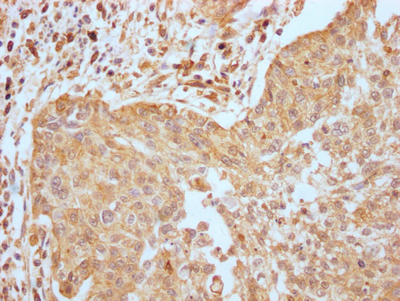

IHC image of CSB-RA794061A0HU diluted at 1:100 and staining in paraffin-embedded human glioma cancer performed on a Leica BondTM system. After dewaxing and hydration, antigen retrieval was mediated by high pressure in a citrate buffer (pH 6.0). Section was blocked with 10% normal goat serum 30min at RT. Then primary antibody (1% BSA) was incubated at 4℃ overnight. The primary is detected by a Goat anti-rabbit IgG polymer labeled by HRP and visualized using 0.05% DAB.

IHC image of CSB-RA794061A0HU diluted at 1:100 and staining in paraffin-embedded human cervical cancer performed on a Leica BondTM system. After dewaxing and hydration, antigen retrieval was mediated by high pressure in a citrate buffer (pH 6.0). Section was blocked with 10% normal goat serum 30min at RT. Then primary antibody (1% BSA) was incubated at 4℃ overnight. The primary is detected by a Goat anti-rabbit IgG polymer labeled by HRP and visualized using 0.05% DAB.